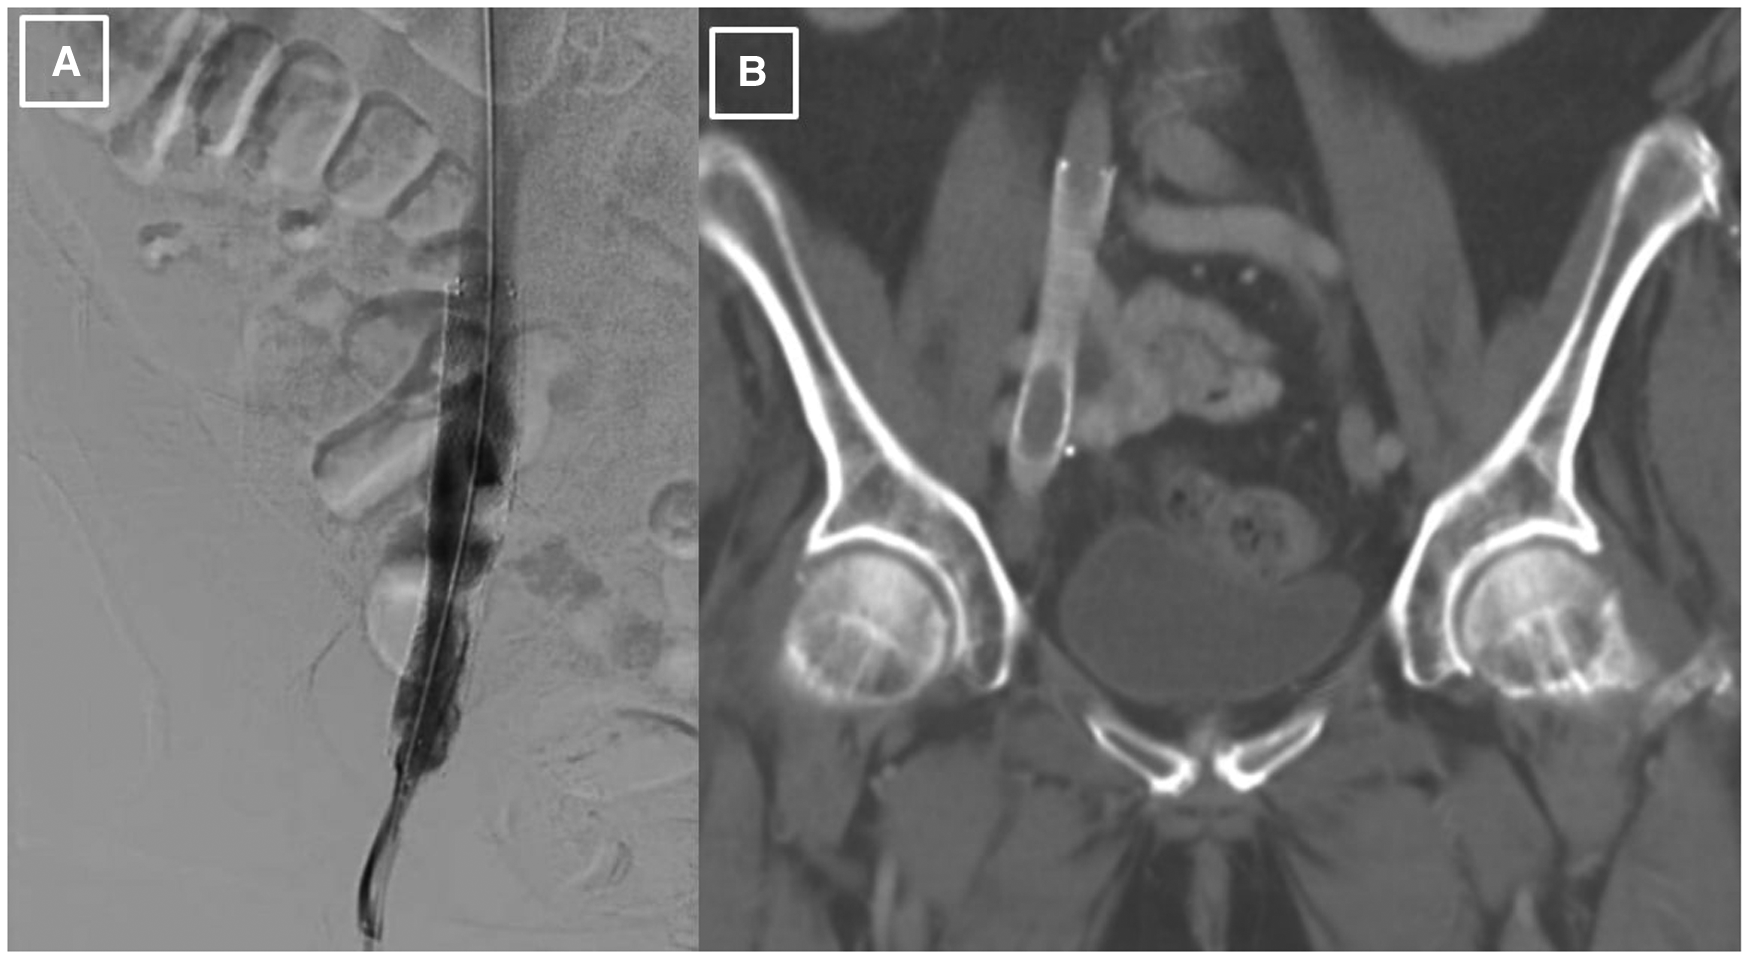

The first step in the patient's diagnostic work-up was a venous Duplex ultrasound test of the right lower extremity, which revealed marked right external iliac vein narrowing with abnormal Doppler waveforms, suggestive of a hemodynamically significant obstructive lesion secondary to external compression. A transthoracic echocardiogram revealed normal left ventricular size and systolic function, mild left atrial dilation, grade 1 diastolic dysfunction, moderate mitral regurgitation, and an elevated estimated right atrial pressure based on the dilated inferior vena cava. To measure the intracardiac pressures, rule out pulmonary hypertension, and better characterize the iliac vein stenosis, the patient underwent right heart catheterization (RHC) with iliac venography. The iliac venogram revealed severe stenosis of the right external iliac vein (Figure 1A), while RHC showed normal intracardiac pressures (normal RAP, mean PAP, and PCWP).

Figure 1

Initial venography, CT and PET imaging of the right external iliac vein. (A). Iliac venography demonstrating severe stenosis of right external iliac vein. (B). CT abdomen pelvis revealing right external iliac lymphadenopathy (LAD), measuring 2.5 × 3.2 × 2.7 cm, marked by blue arrow. (C). CT abdomen pelvis demonstrating severe right sided hydronephrosis due toR ureteral external compression by mass burden, marked by blue arrow. (D, E). PET scan redemonstrating R external iliac LAD.

Given her history of endometrial carcinoma, the possibility of extrinsic compression of the iliac vein by tumor was considered. Thus, a computed tomography (CT) scan of the abdomen/pelvis with and without intravenous (IV) contrast was obtained. The results indicated a markedly enlarged and necrotic right external iliac lymph node (2.5 × 3.2 × 2.7 cm) which was causing external compression of, and likely invading, the right iliac vein (Figure 1B). Significant compression of the right ureter associated with severe right-sided hydronephrosis (Figure 1C) and right pelvic sidewall lymphadenopathy were seen as well. Next, a full-body PET scan was ordered for staging purposes, demonstrating metabolic activity in the right external iliac lymph node and an area of increased activity in the left adrenal gland (Figures 1D, E). After a multidisciplinary discussion, the patient was offered an endovascular intervention of the iliac vein with stenting to improve her refractory right lower extremity edema.

Since there was a high probability of cancer invading the vessel wall and the right ureter, a decision was made for palliative endovascular stent placement to provide symptomatic relief and to avoid the risks of an open surgical approach, including intra-operative and post-operative bleeding. The patient was taken to the cardiac catheterization laboratory, where an intravascular ultrasound (IVUS) was performed to visualize the lesion and to measure the lesion length and the reference diameter for choosing the correct size of the stent. After the lesion was crossed with a 0.035 angled glide guide wire, the patient underwent right external iliac vein balloon angioplasty followed by the successful placement of a VICI 14 × 90 mm stent, VENITI, INC., Fremont, CA. Post-dilation was done with a 10 × 60 mm balloon at 8 atmospheres and a 14 × 60 mm balloon at 4 atmospheres. The follow-up IVUS showed a re-canalized iliac vein with normal venous flow and 100 mm2 of luminal gain at the previously occluded point. The re-canalization was additionally re-demonstrated on an abdominal/pelvic CT scan (Figures 2A, B).

Post-procedural imaging of the stented right external iliac vein. (A). Iliac venography status post IVUS-guided visualization and right external iliac vein balloon-angioplasty with successful placement of VICI 14 × 90 mm stent and resultant patency. (B). CT abdomen pelvis demonstrating presence of stent within the R external iliac vein prior to abdominal debulking procedure.